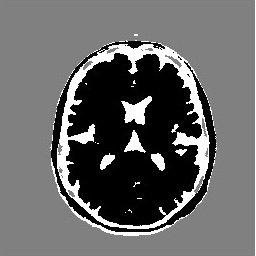

We illustrate the performance of Algorithm 1 when applied to the well-known MRI and cameraman images. Figure 1 shows results of completion for the MRI image determined by Algorithm 1, the CNC algorithm [17], and the ATCG-TV algorithm [4] for 90%90\% missing data (SR=0.1=0.1). Table 1 reports PSNR-values, CPU-times (in seconds), and the number of iterations (Iter) required by each algorithm to satisfy the stopping criteria. The stopping criteria for the ATCG-TV and CNC algorithms were the default choices provided in [4] and [17], respectively.

Refer to caption Refer to caption Refer to caption Refer to caption Refer to caption

Original Observed CNC ATCG-TV LR-CNC

Fig. 1: Recovered MRI images by the CNC, ATCG-TV, and LR-CNC algorithms for SR=0.1=0.1.

MRI 0.1 21.22 20.22 730 18.44 8.20 968 21.36 4.54 174

0.2 23.14 5.68 355 21.96 7.13 782 23.37 2.69 98

0.3 25.01 4.00 262 24.37 8.56 889 25.32 1.65 60

Cameraman 0.1 21.34 11.53 757 19.31 6.58 770 21.52 5.09 184

0.2 23.11 5.52 361 22.11 7.31 785 23.27 2.64 91

0.3 24.33 3.35 220 24.08 6.90 755 24.70 1.66 58

Table 1: PSNR-values of the restored images, CPU-times, and number of iterations by the CNC, ATCG-TV, LR-CNC methods for various values of SR.

Figure 1 and Table 1 show that for small SR-values, the LR-CNC algorithm outperforms the ATCG-TV algorithm. However, for larger SR-values, the difference in performance between the two algorithms is less significant. The LR-CNC algorithm demonstrates a clear advantage in terms of CPU time and the number of iterations required in comparison with both the CNC and ATCG-TV algorithms. Figure 2 displays the graphs of the logarithm of the mean square error versus the number of iterations for the LR-CNC, CNC, and ATCG-TV algorithms, as well as the values of